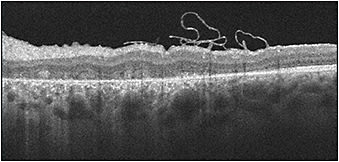

My colleagues and I have employed the inverted ILM flap technique many times. We recently used it to close a macular hole in a 22-year-old male patient who was referred to us after a deployed vehicle airbag caused blunt trauma to his left eye. At presentation, visual acuity OS was hand motion (Figure 1). We performed pars plana vitrectomy and ILM peeling utilizing ICG, leaving a flap of ILM intact. We inverted the flap over the center of the whole, in effect plugging the hole with the tissue. We used intraoperative OCT to verify that the flap was in proper position. Postoperatively, macular edema resolved and visual acuity improved to 20/400 (Figure 2). The scotoma that had been present decreased in size. We didn’t expect visual acuity to improve further, given the duration of the condition in this case. Visual acuity following surgical repair of traumatic macular hole varies based on the presence or absence of concomitant conditions and the amount of trauma an eye suffers. Many of our patients who experienced minor trauma have done quite well.